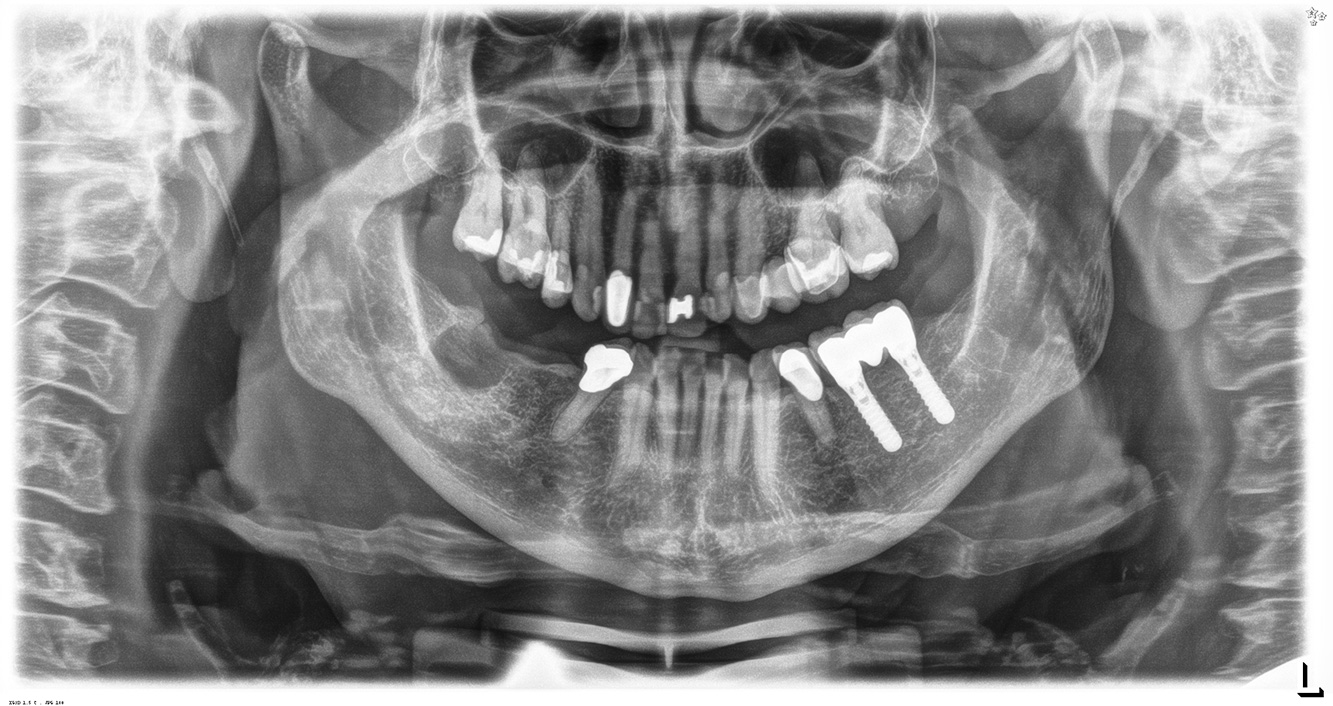

The healthy patient with pre-existing periodontal disease & peri-implantitis

A 52-year-old patient presents at a preventive care session. The patient has no systemic disease and is not taking any medication. He has had various dental treatments and also has two active carious lesions. In addition, the patient has four implants (2nd, 3rd and 4th quadrants). He is revealed to have early periodontal disease (stage IV, grade B). His periodontal condition is stable; a probing depth of Probing depths (ST) of 5 mm is only evident at the implant in region 36. Gingivitis is also identified. more